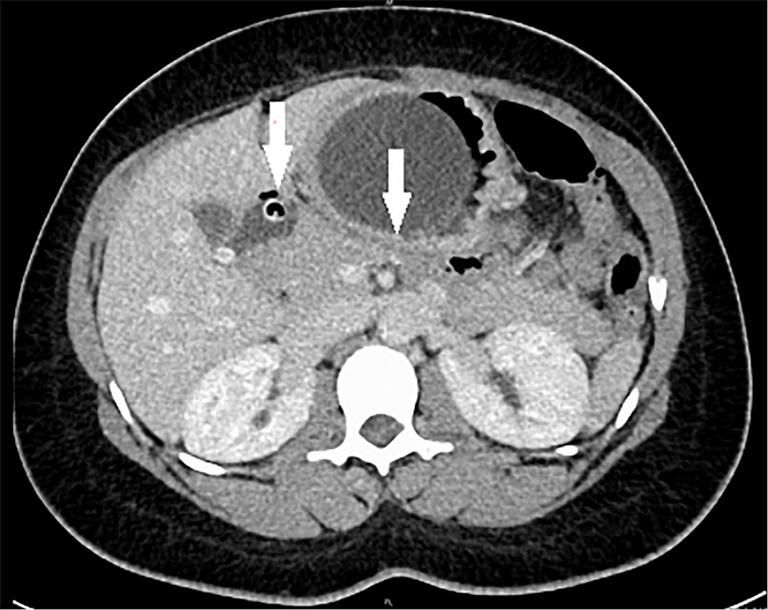

We present the case of a 28-year-old woman who underwent IGB insertion 9 months before onset of intense upper abdominal pain. We confirmed the diagnosis of acute pancreatitis by means of clinical symptoms, serological tests and cross-sectional imaging. Endoscopic removal of the balloon led to a complete resolution of the symptoms. Initial laboratory parameters were normal on admission, only the control of lipase and amylase levels led us to the diagnosis of pancreatitis. On imaging with computed tomography, the filling catheter of the balloon showed to be dislodged in the duodenum. After carrying out a systematic approach, other causes of pancreatitis were ruled out.

我们报告一例28岁女性病例,该患者在剧烈上腹部疼痛发作前9个月接受了胃内球囊置入术。我们通过临床症状、血清学检查和断层成像确诊为急性胰腺炎。内镜下取出球囊后症状完全缓解。入院时初始实验室参数正常,仅通过监测脂肪酶和淀粉酶水平才确诊为胰腺炎。在计算机断层扫描成像中,球囊的填充导管显示位于十二指肠内。经过系统排查,排除了其他胰腺炎病因。